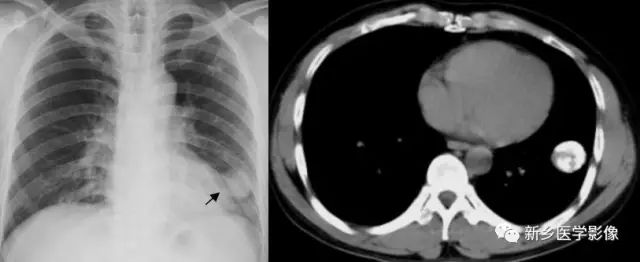

肺脓肿空洞CT图

a. 肺窗;b.纵隔窗,显示右上肺厚壁空洞(↑)周围见大片状模糊影

肺空腔CT图

a. CT肺窗显示两上肺大泡 b. CT肺窗显示左下支气管扩张